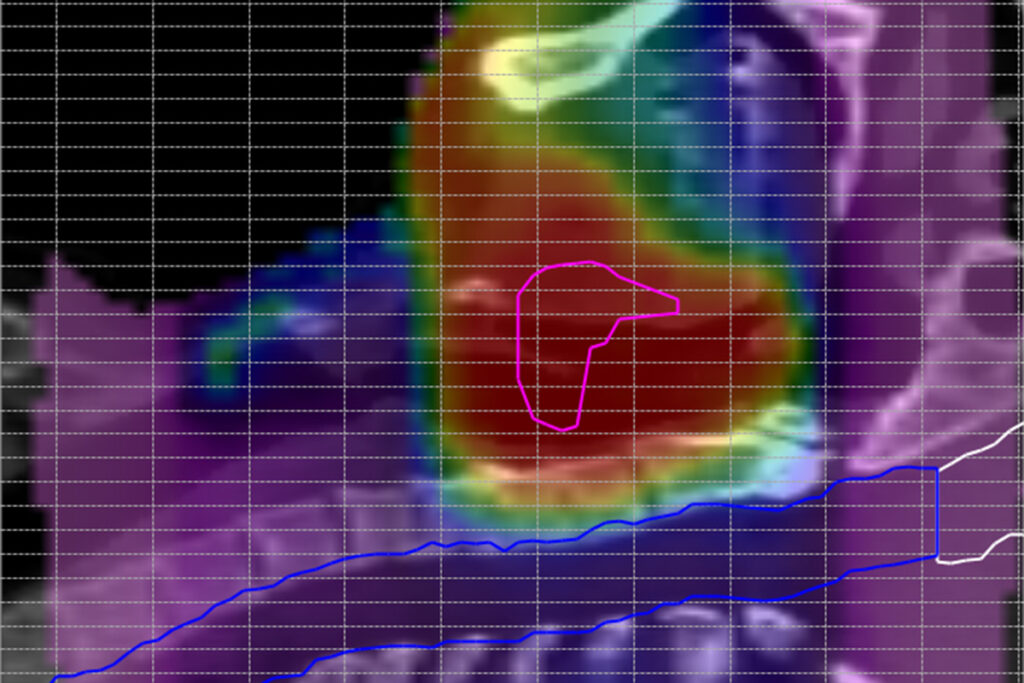

Dose verification in the patient anatomy

With the Delta4DVH Anatomy software option, you can verify and analyze the dose that has been delivered to the patient anatomy. Based on the measurements in the isocentric target region and dose calculation of the dose in the patient anatomy you now have a truly independent verification of the delivered dose.

Analyze the dose delivered to the patient anatomy